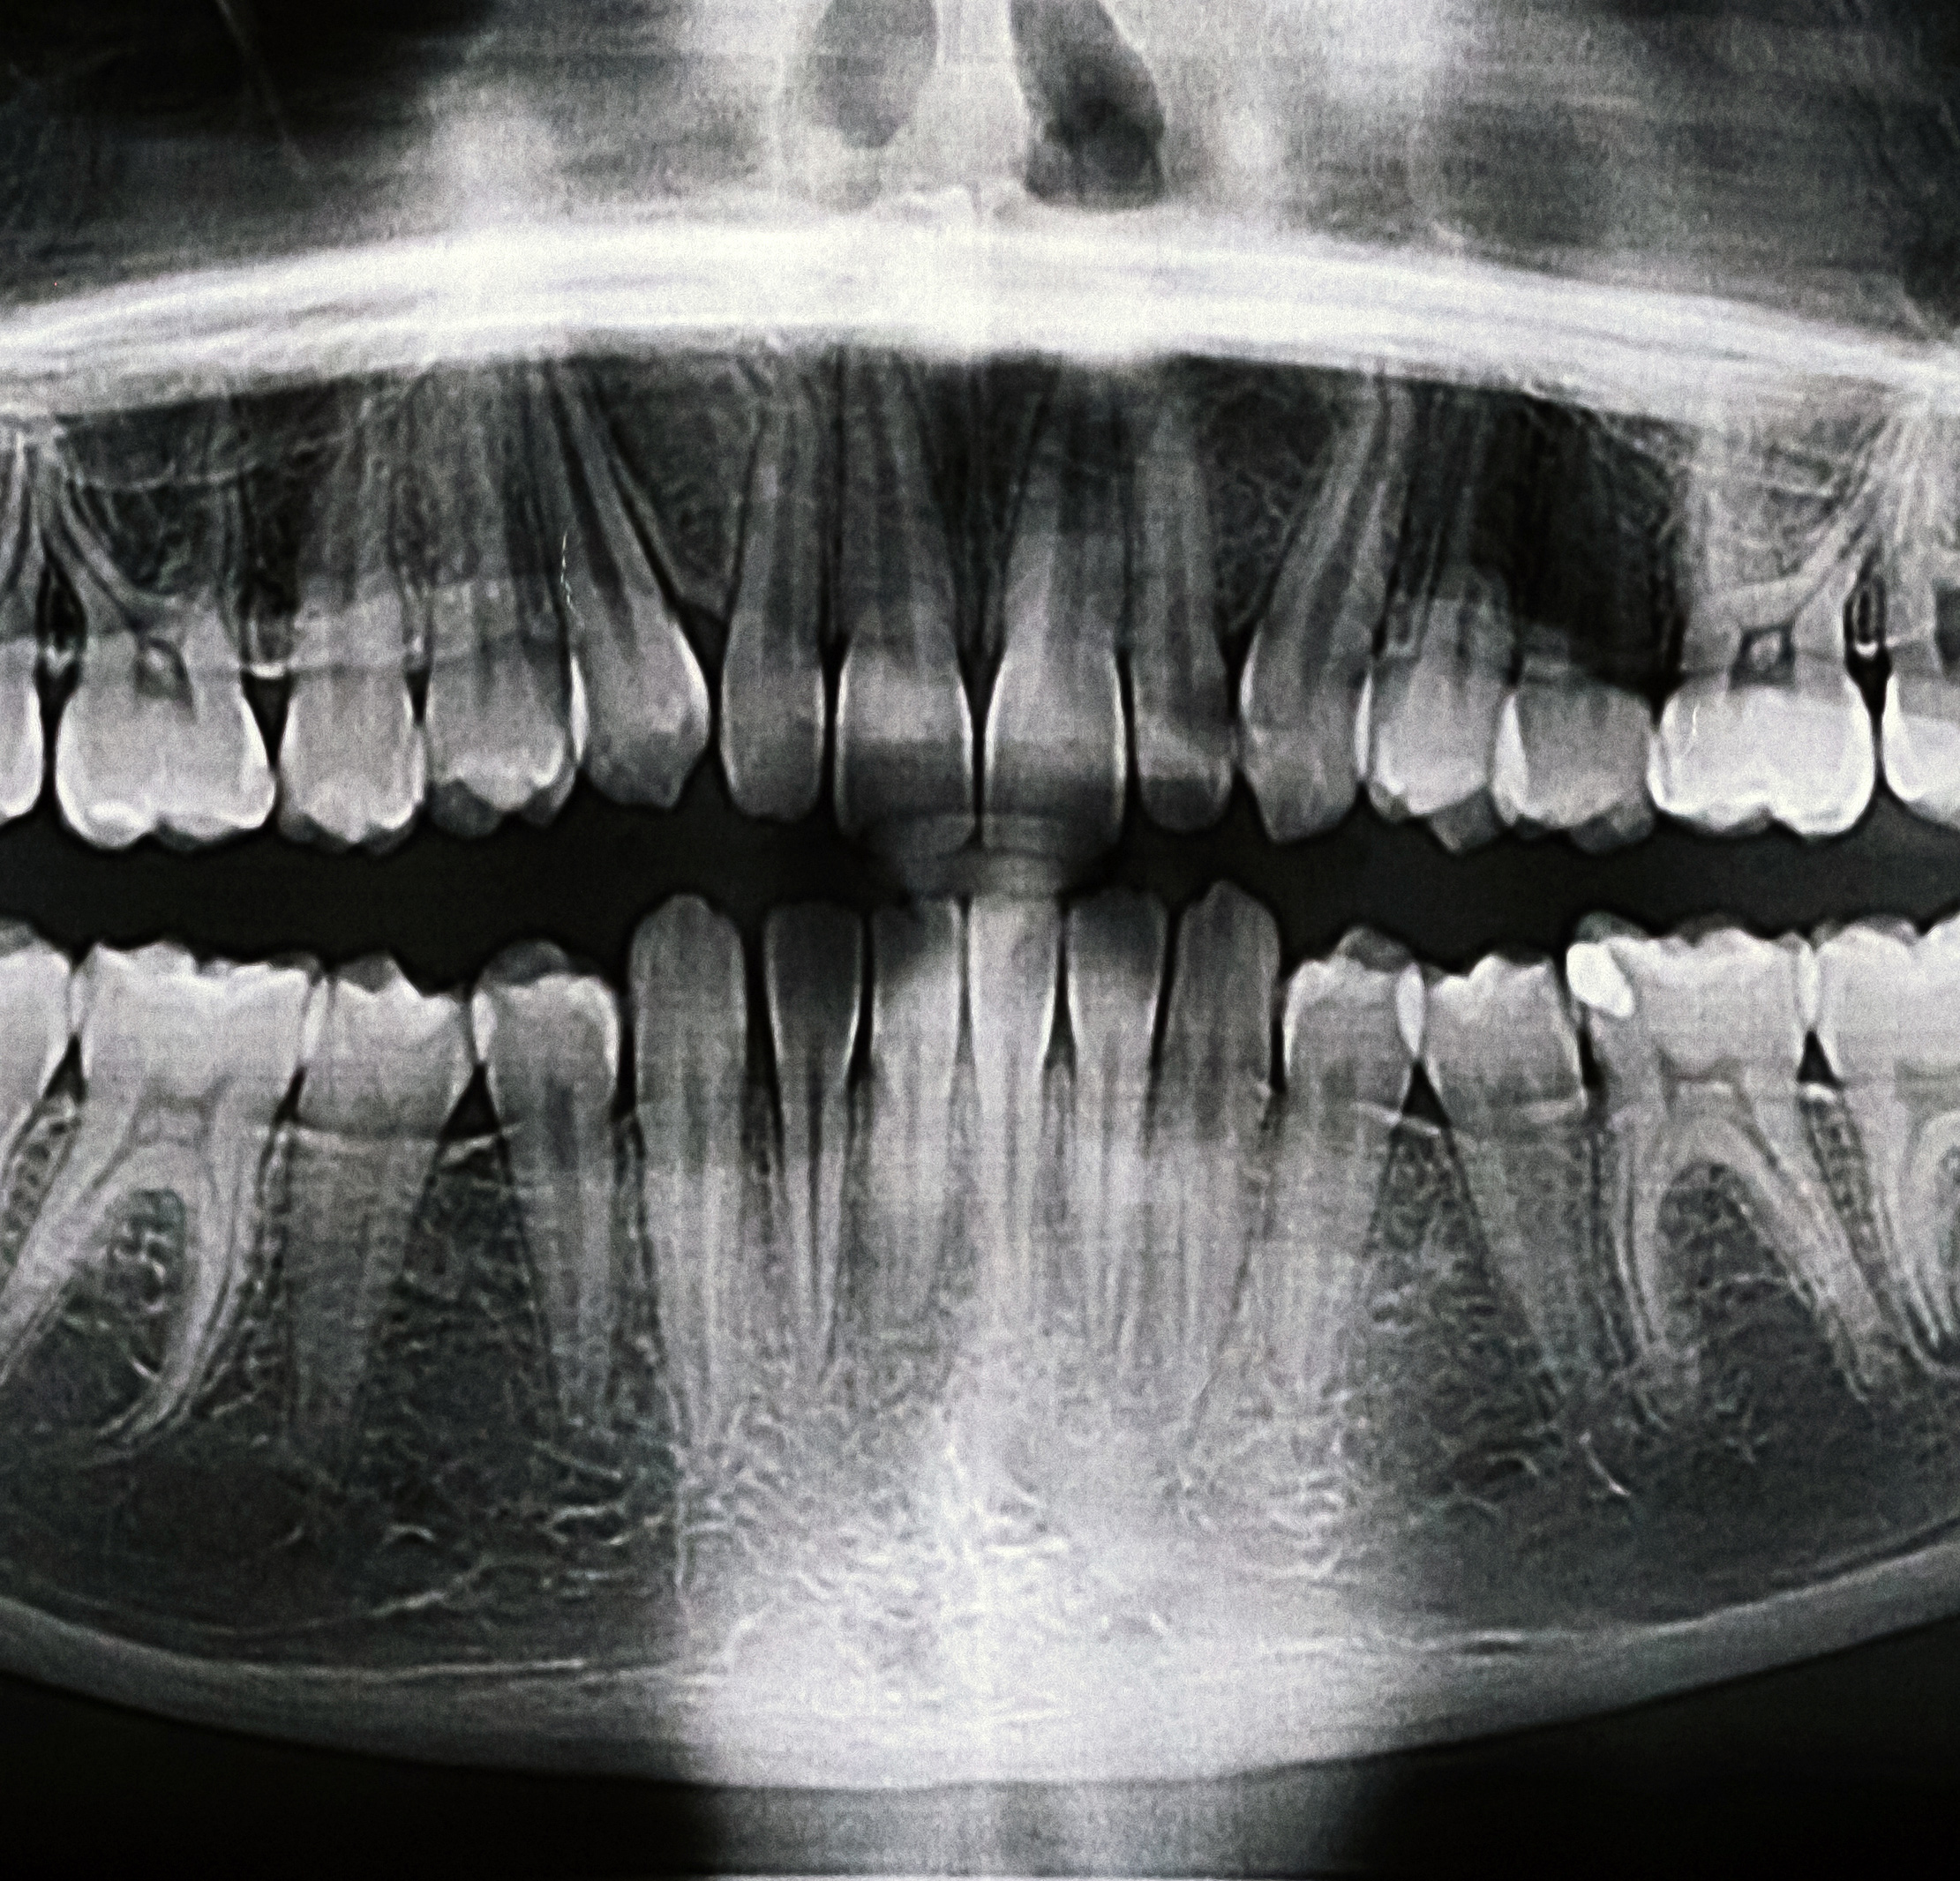

1. Radiografia panoramică

• Oferă o vedere completă a maxilarului superior și inferior

• Permite evaluarea dinților, articulațiilor temporomandibulare și structurilor osoase

• Utilă pentru: planificarea implanturilor, evaluarea dinților incluși și screening general